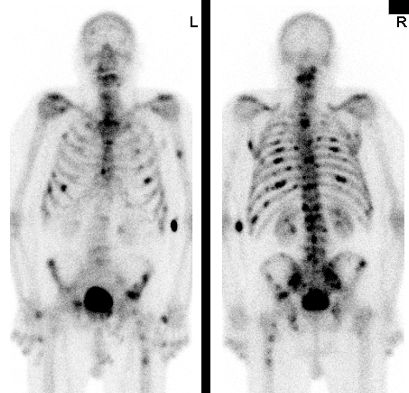

77-jähriger Mann mit Rückenschmerzen. PSA 1700! Im

Knochenszintigramm Hinweis auf diffuse Knochenmetastasierung.![]() | ||||||||||||||||||||

75-jähriger Mann, der wegen unklarer Schmerzen im

Nackenbereich abgeklärt wurde. Als Ursache der Knochenmetastasen wurde ein lokal

fortgeschrittenes Prostatakarzinom (PSA 143, Gleason 7) gefunden.![]() |